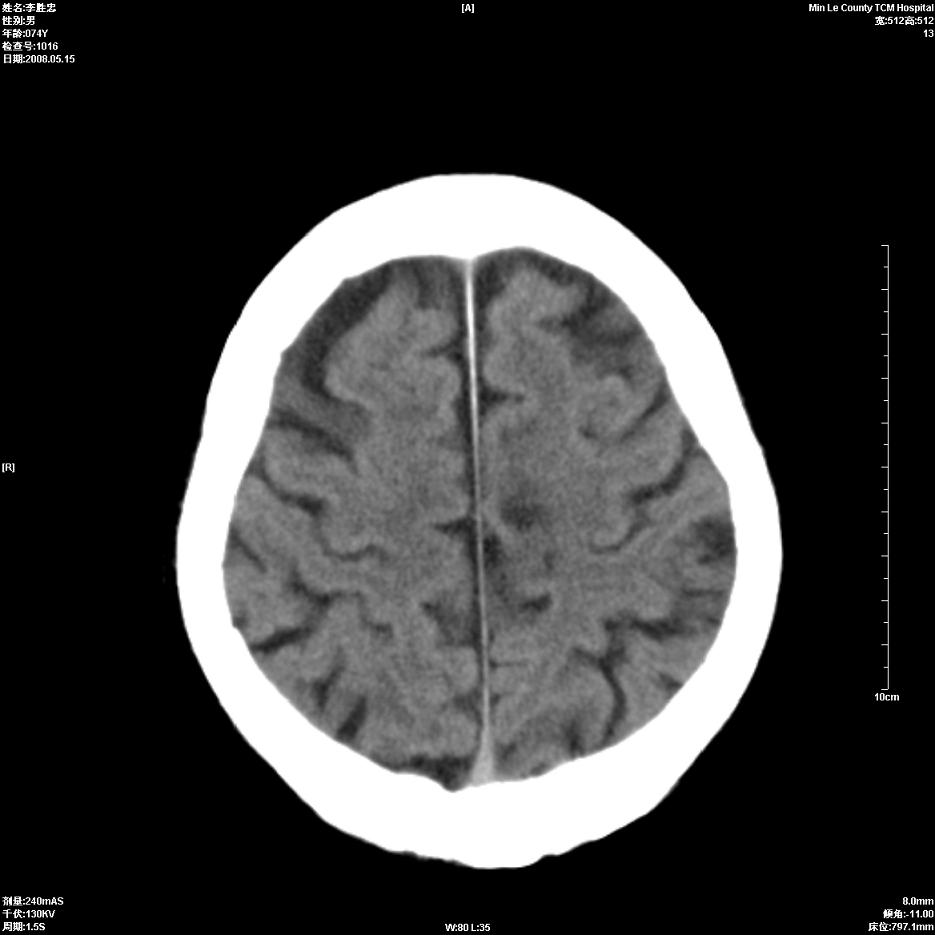

以下是引用hhcckk在2008-5-30 14:26:00的发言:[br]病灶跨中线,有占位效应,强化不明显,考虑胼胝体区低级别的星形细胞瘤可能性大,建议mr检查